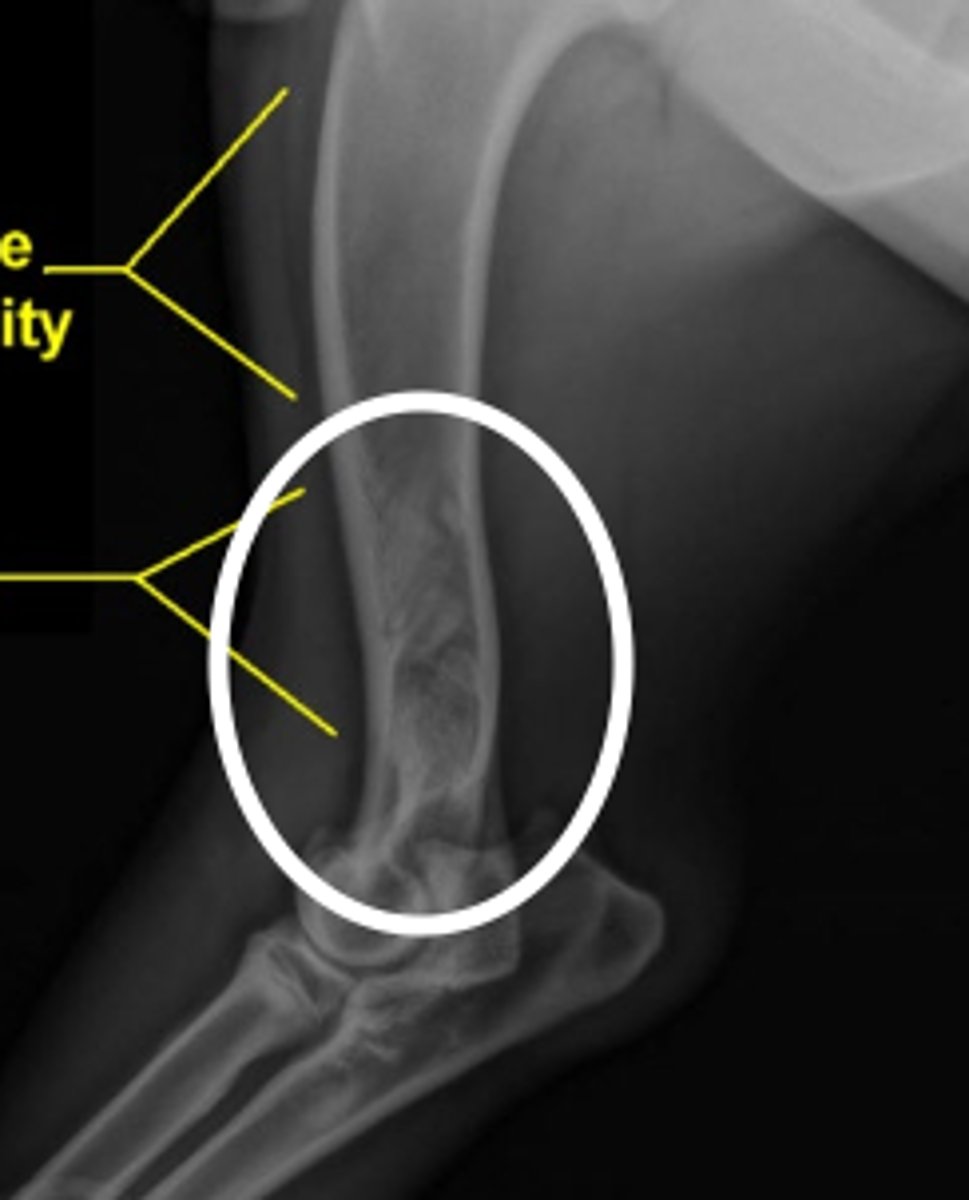

superficial layer of the bone (periosteum) becomes painfully inflamed in YOUNG animals (while it is still growing)

what is panosteitis?

panosteitis

what is the problem here?